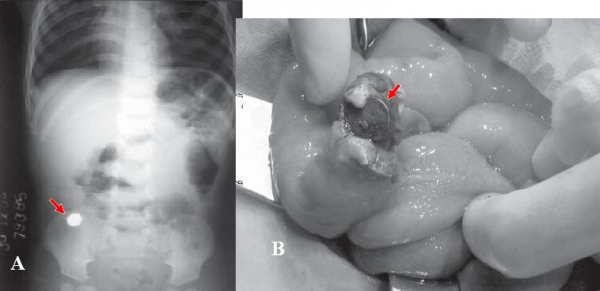

Dò túi thừa Meckel do dị vật rất hiếm gặp và thường xảy ra ở trẻ em. Những dị vật tăm xỉa răng, xương cá, xương gà, nút pin .. đã được báo cáo.

Hình 31: Thủng túi thừa Meckel ở bệnh nhân nam 1 tuổi bị bệnh Crohn. A, X quang thấy dị vật cản quang tròn ở hố chậu phải (mũi tên). B, túi thừa Meckel hoại tử thủng do dị vật là pin lithium 10 x 3 mm ( mũi tên). (AYS¸E KARAMAN, I˙BRAHI˙M KARAMAN (2007). Perforation of Meckel’s Diverticulum by a Button Battery: Report of a Case. Surg Today 37:1116.).